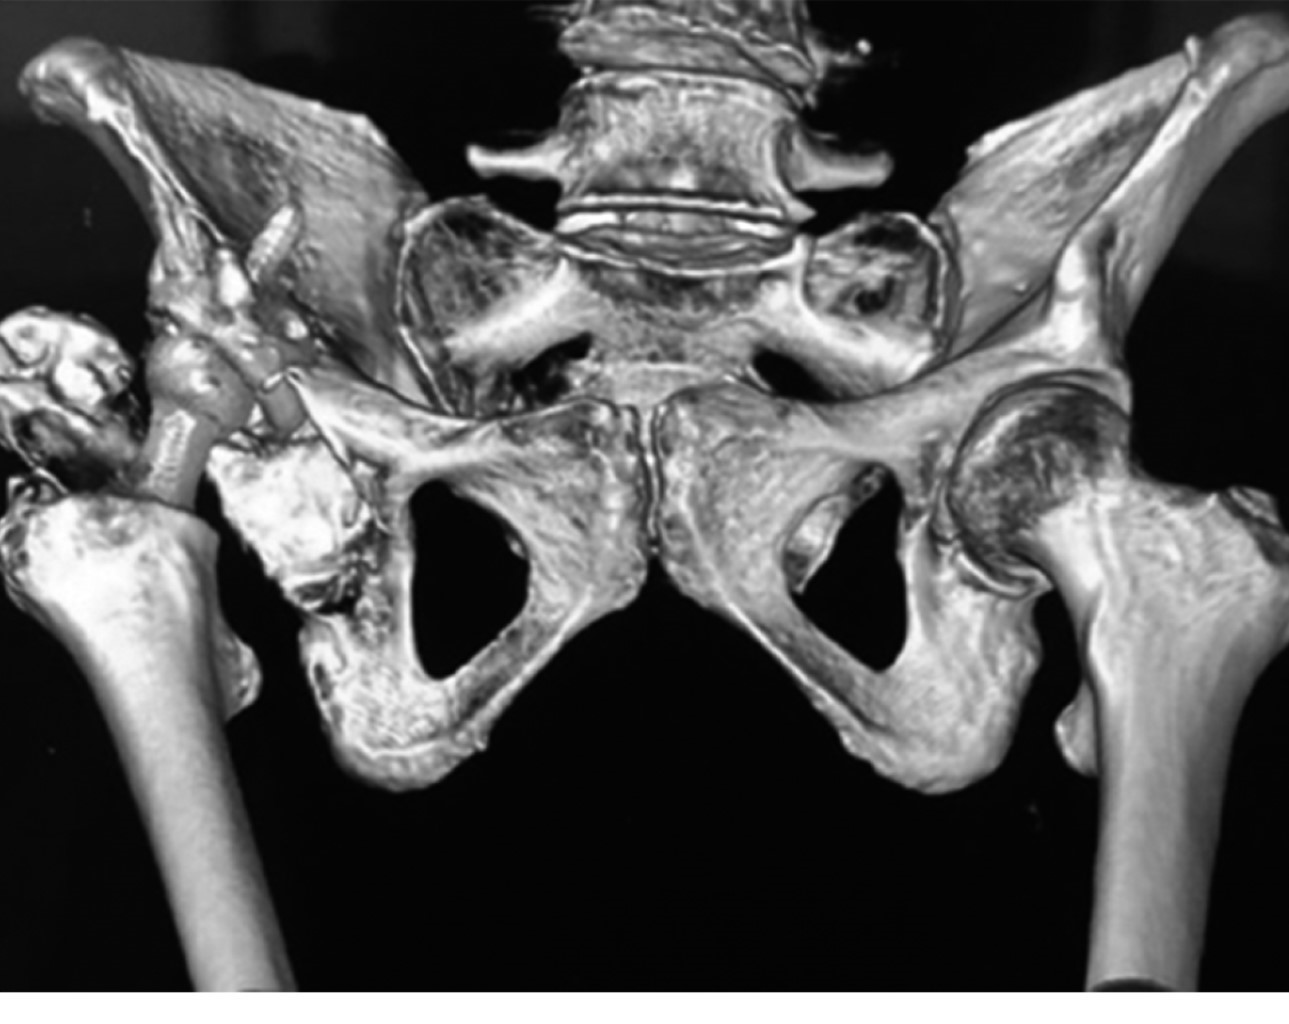

Paciente femenino de 71 años que se somete a artroplastía primaria total de cadera derecha secundaria a coxartrosis, con un resultado quirúrgico no satisfactorio en radiografía de control al finalizar la colocación de los componentes debido a una mala orientación del componente acetabular (Figuras 1 y 2), dejando una zona de pérdida en el techo acetabular original. Se decide en ese momento la conservación de la cabeza femoral en tejidos blandos para colocar como injerto en segundo tiempo quirúrgico (Figura 3), el cual se realizó dos semanas posteriores al primer procedimiento, reconstruyendo defecto con injerto de cabeza y fijándolo con tornillos acetabulares 6.5 mm. El componente acetabular constó de una copa Refletion (Smith & Nephew, Memphis, TN, USA) de recubrimiento poroso fijada con tres tornillos acetabulares 6.5 mm y vástago no cementado Synergy (Smith & Nephew, Memphis, TN, USA).

Figura 1